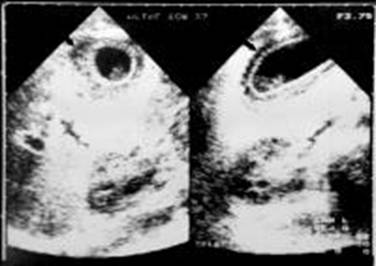

L'ecotomografia è quasi da sempre indagine di prima istanza nello studio della patologia infiammatoria della colecisti, per la semplicità di esecuzione e i bassissimi costi. L'esame è effettuato a paziente inizialmente in decubito supino, con approccio sottocostale, in inspirazione profonda per poter utilizzare la finestra acustica epatica, e successivamente in decubito obliquo posteriore sinistro, con approccio intercostale, in espirazione profonda per allontanare l'aria dai seni costo diaframmatici. Si eseguono scansioni longitudinali e trasversali rispetto all'asse principale della colecisti.

I criteri morfologici ultrasuonografici tipici di colecistite acuta possono essere classificati in maggiori e minori.

Tra i maggiori:

- Calcoli in sede colecistica (presenti in più del 90% dei pazienti);

1) Spessore della parte colecistica di più di 3mm;

2) Fluido pericolecistico (segno di una attuale o imminente perforazione d'organo);

3)Slaminamento della parete (indicativo di edema infiammatorio);

4) Positività al segno ecografico di Murphy (dolore slatentizzato alla compressione della colecisti attraverso la sonda ecografica);

5) Gas intramurale (segno indicativo di colecistica enfisematosa);

I criteri minori

includono la presenza di sludge biliare nella colecisti e un aumento del suo

diametro trasverso di più di

Per confermare la diagnosi di colecistite acuta è necessaria la presenza di due criteri maggiori oppure uno maggiore e due minori.

La diagnosi della colecistite acuta è rapida, non invasiva, facilmente eseguibile e molto sensibile, anche se purtroppo, operatore dipendente.

La sensibilità e la specificità dell'esame ultrasonografico nella colecistite acuta sono rispettivamente dell'81-100% e del 60-100%. 13 ,14

Fig 3 Esame ultrasonografico dell'addome . slaminamento della parete colecistica

Fig 4 Esame ultrasonografico dell'addome . slaminamento della parete colecistica